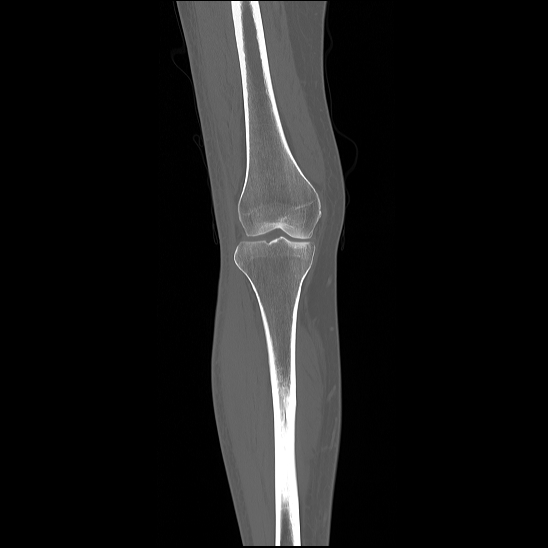

We test our algorithm on the tomographic reconstruction of two objects. The first is the Shepp–Logan phantom, and the second is a computed tomography of a knee taken from Ref. [32]. See Figure 5.6. In this experiment, we generate random points uniformly distributed in . The parameters used in Algorithm 3 are , and . The tomographic projections are computed using Matlab ‘s radon function. We add random noise to these projections, for that, we consider the dataset of the form

In Figures 5.9 and 5.10, we plot the reconstructed images of the Shepp–Logan phantom and the knee tomography, respectively. Here, the samples of the angles are uniformly distributed over . We consider different levels of additive order error as represented in Eq. (5.16). We remark that we obtained similar results to those shown using multiple executions of our method. To measure the effectiveness of our method, we compare the error generated when our algorithm is implemented. The computed error is shown in Tables 1 and 2. Observing the computational error and image quality, we conclude that our reconstruction algorithm works efficiently with relatively low computational cost.